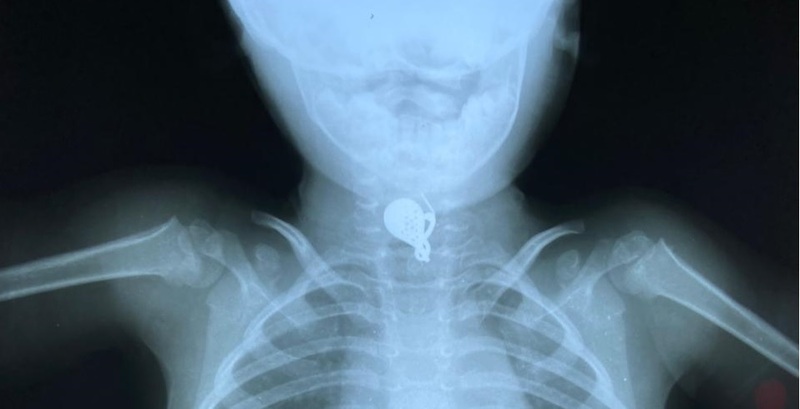

No exame de raio X a equipe conseguiu observar o ponto exato onde estava o brinco para fazer o procedimento. A menina já recebeu alta do HU de Maringá e voltou para a cidade de Paraíso do Norte com os pais.